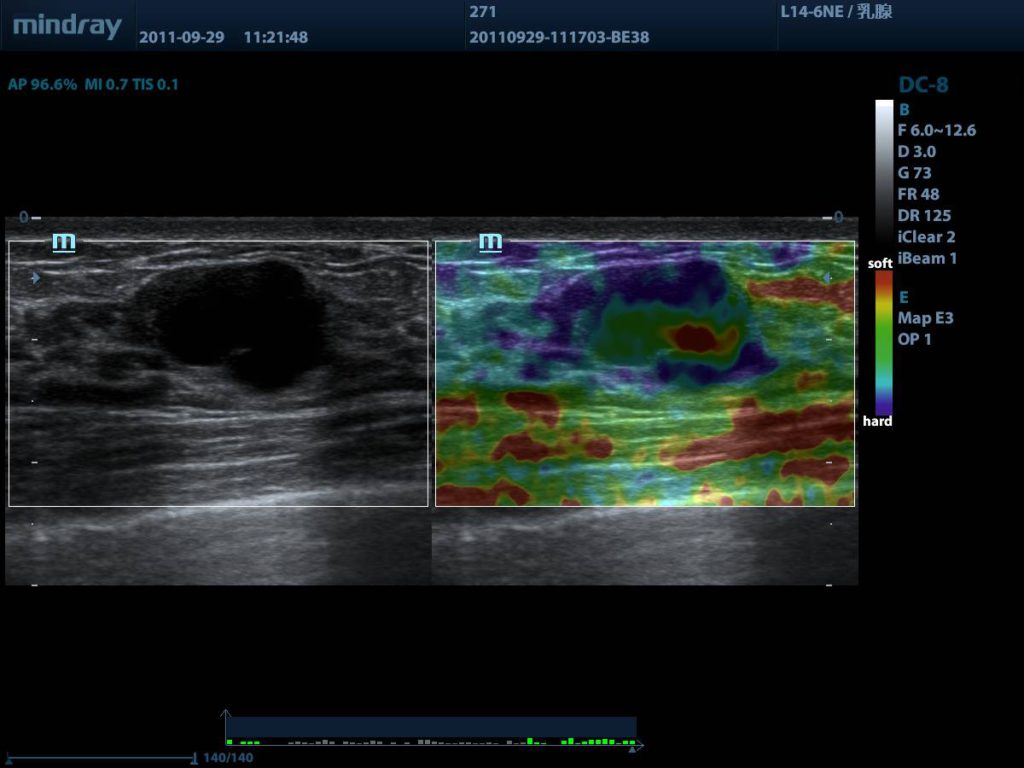

Breast cyst elastogrphy